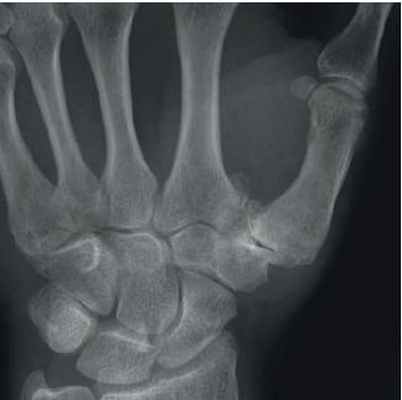

Дифференциальная диагностика заболеваний кисти

Рентгенография – отек мягких тканей вокруг суставов, остеопороз, сужение суставных щелей, краевые эрозии, субхондральные кисты и подвывихи, деформации кистей; вовлечение подтаранного сустава, эрозия заднего бугорка пяточной кости; эрозия дистальной части ключицы, краевые эрозии головки плечевой кости, субакромиальный бурсит; остеоартрит тазобедренных суставов с сужением суставных щелей; синовит коленного сустава, препателлярный бурсит; атланто-аксиальные подвывихи, эрозия зуба и остистых отростков.

Ревматоидный артрит. Эрозии головок метакарпальных костей. Сужение средних суставов пальцев.

Рентгенография: эрозивный остеоартрит в острой фазе с поражением дистальных и проксимальных межфаланговых суставов – субхондральные и центральные эрозии, но нет краевых эрозий; остеоартроз в хронической фазе (субхондральный склероз, остеофиты) и анкилоз

Остеартрит с типичным поражением первого карпо-метакарпального сустава. Сужение суставной щели. Остеофиты, субхондральный склероз.

Псриатический артрит. Поражение дистальных фаланг с эрозиями и костной формацией ( палец).